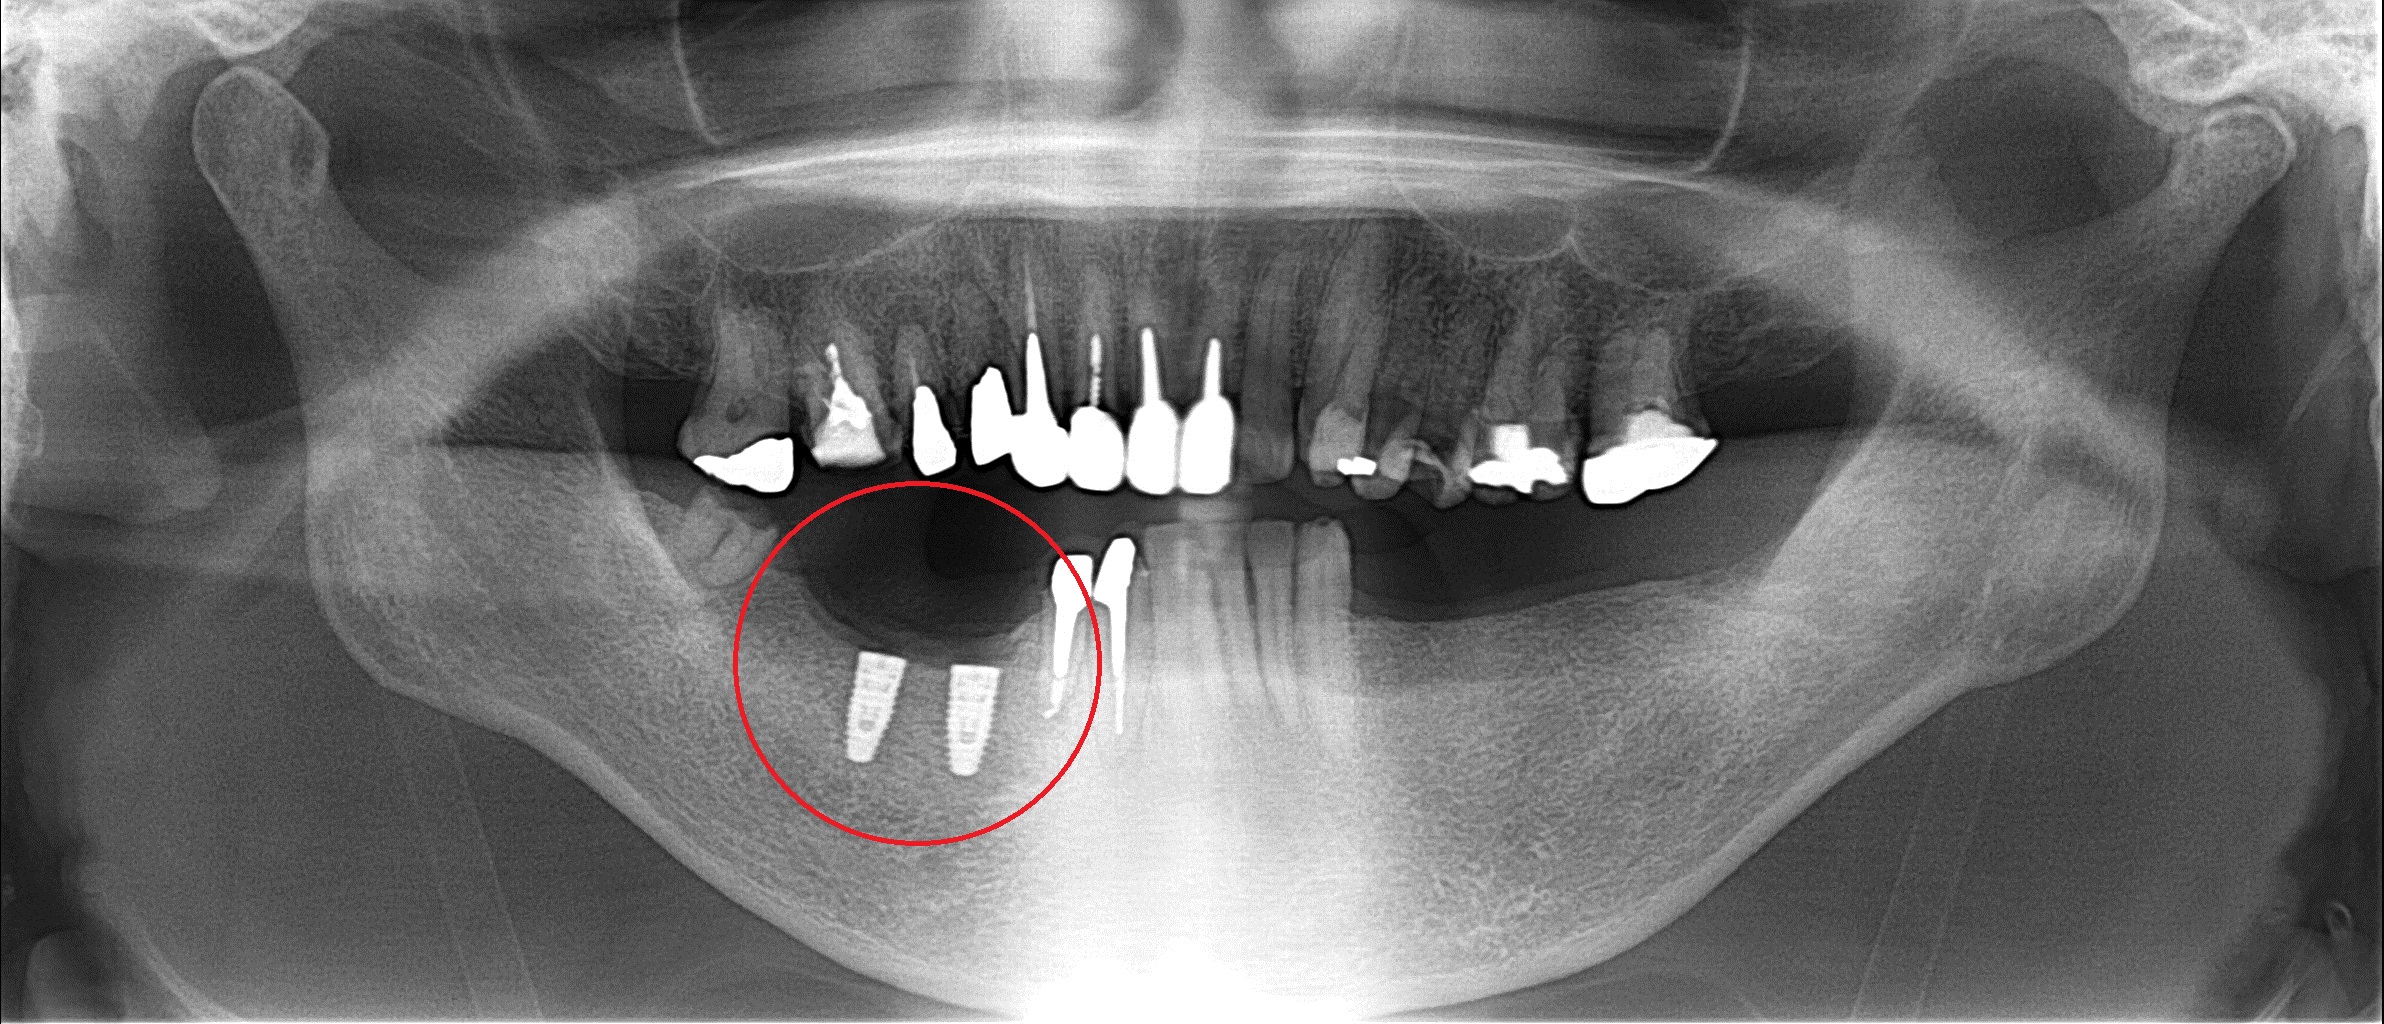

まずは右下の赤い丸の部分に埋入させてもらいました。

上の奥歯と下の歯ぐきが引っ付きそうになっている

長期間、奥歯がない状態だったようで

レントゲンからは分りにくいかもしれませんが

咬んだ時に上の奥歯と下の歯ぐきが

引っ付きそうになっています。

咬み合わせを全て元に戻すのが理想ですが

時間と金銭的に困難だったので

少し骨を細工させてもらいました。